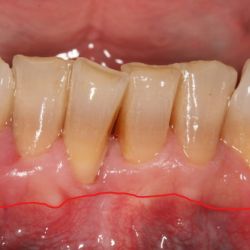

Caso de cirugía periodontal

Cirugía periodontal en un paciente